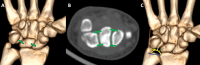

Wrist fractures and dislocations are frequently encountered in the emergency department and can cause significant long-term disability. Imaging plays a crucial role in the evaluation of wrist injuries, with conventional radiography being the first imaging investigation. Cross-sectional imaging is playing an increasingly important role in management of wrist injuries. Computed tomography with 3D and multiplanar reformatting capabilities is in particular useful for detailed evaluation of bony injuries and can provide vital information to orthopaedic surgeons for adequate surgical planning. In this article, we provide a brief review of the normal wrist anatomy, imaging appearance, and various patterns of fractures and dislocations commonly encountered in the emergency department.